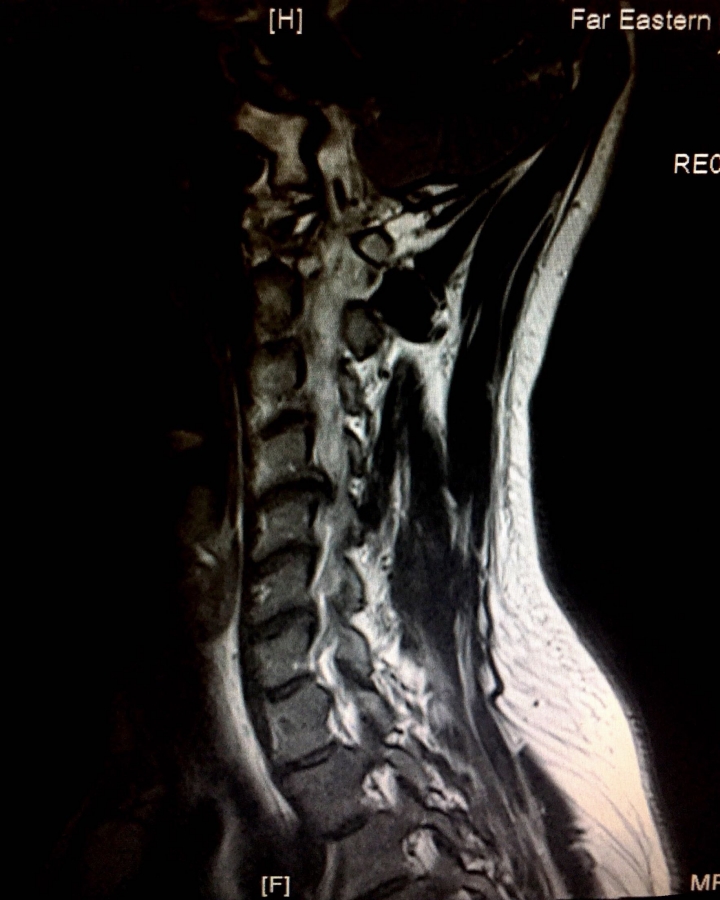

小弟住台北30歲前些日子去醫院照MRI醫生說我頸椎間盤突出壓到神經3 、4 、5 、6尤其已5 、6最為嚴重,建議我復健但復健不見得有用,但我年紀才30醫生建議我不要開刀因為我症狀只有右手的大拇指有一點麻肩頸有點緊跟頭有時會昏昏的,醫生說不明顯,但我還是覺得不舒服,上網查椎間盤突出治療有分幾種,有分傳統手術、微創手術又有分低溫電漿療法(據說副作用較小)我想請問大家有推的醫院或醫生嗎?或者其他治療方式嗎?感謝大家。以上附上我照MRI跟X光的照片

您那個照片突出往脊髓方向,這個要小心了

您好像有頸椎變形,似乎弧度不對